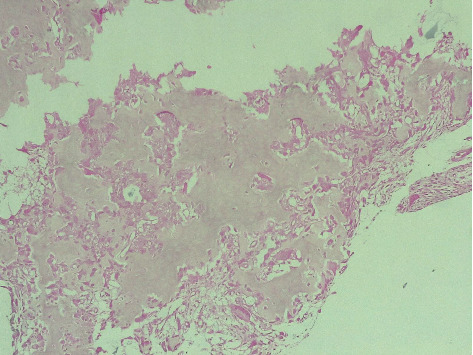

Figure 4.

Histopathology of the osteoid osteoma (Haematoxylin and Eosin × 400).

Given the exclusion of early inflammatory rheumatic diseases (IRD) and joint infections, and the predominant unexplained bone edema observed on MRI, a computed tomography (CT) scan was warranted to further assess bone structure and investigate potential underlying lesions. The indication for CT was further reinforced by follow-up radiographs (Figure 1(c)), which revealed well-defined sclerotic lesions in the trapezoid and the base of the second metacarpal bones, raising suspicion of a benign bone tumor or another structural abnormality requiring further characterization. The CT scan (Figure 3) revealed an intra-articular focal lucent nidus in the trapezoid bone, surrounded by a sclerotic reactive lesion involving both the trapezoid and the base of the second metacarpal bones. This led to the diagnosis of an OO with atypical location and presentation. The patient underwent surgical treatment via a dorsal approach. Intraoperatively, it was observed that the OO in the trapezoid bone extended to the base of the second metacarpal bone. An en bloc tumor excision was performed without reconstructive bone surgery. The gross specimen revealed a red, granular area surrounded by sclerotic bone, measuring 1.5 cm. Histopathological examination identified a network of short, anastomosing trabeculae of osteoid, lined by regular osteoblasts with a few osteoclasts embedded in central hypervascularized loose connective tissue, confirming the diagnosis of OO (Figure 4). Following the surgical excision, the patient experienced immediate pain relief and a gradual improvement in wrist motion and function. Fourteen months post-surgery, she reported no discomfort or functional limitations in the affected extremity and had returned to work. Postoperative radiography showed changes in the bone structure of the trapezoid and the second metacarpal bone (Figure 1(d)).